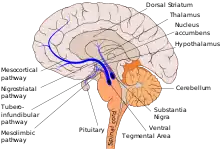

The mesocortical pathway is a dopaminergic pathway that connects the ventral tegmentum to the prefrontal cortex. It is one of the four major dopamine pathways in the brain. It is essential to the normal cognitive function of the dorsolateral prefrontal cortex (part of the frontal lobe), and is thought to be involved in cognitive control, motivation, and emotional response.[1][2]

This pathway may be the brain system that is abnormal or functioning abnormally in psychoses, such as schizophrenia.[3] It is thought to be associated with the negative symptoms of schizophrenia, which include avolition, alogia and flat affect. This pathway is closely associated with the mesolimbic pathway, which is also known as the mesolimbic reward pathway.

Other major dopamine pathways include: